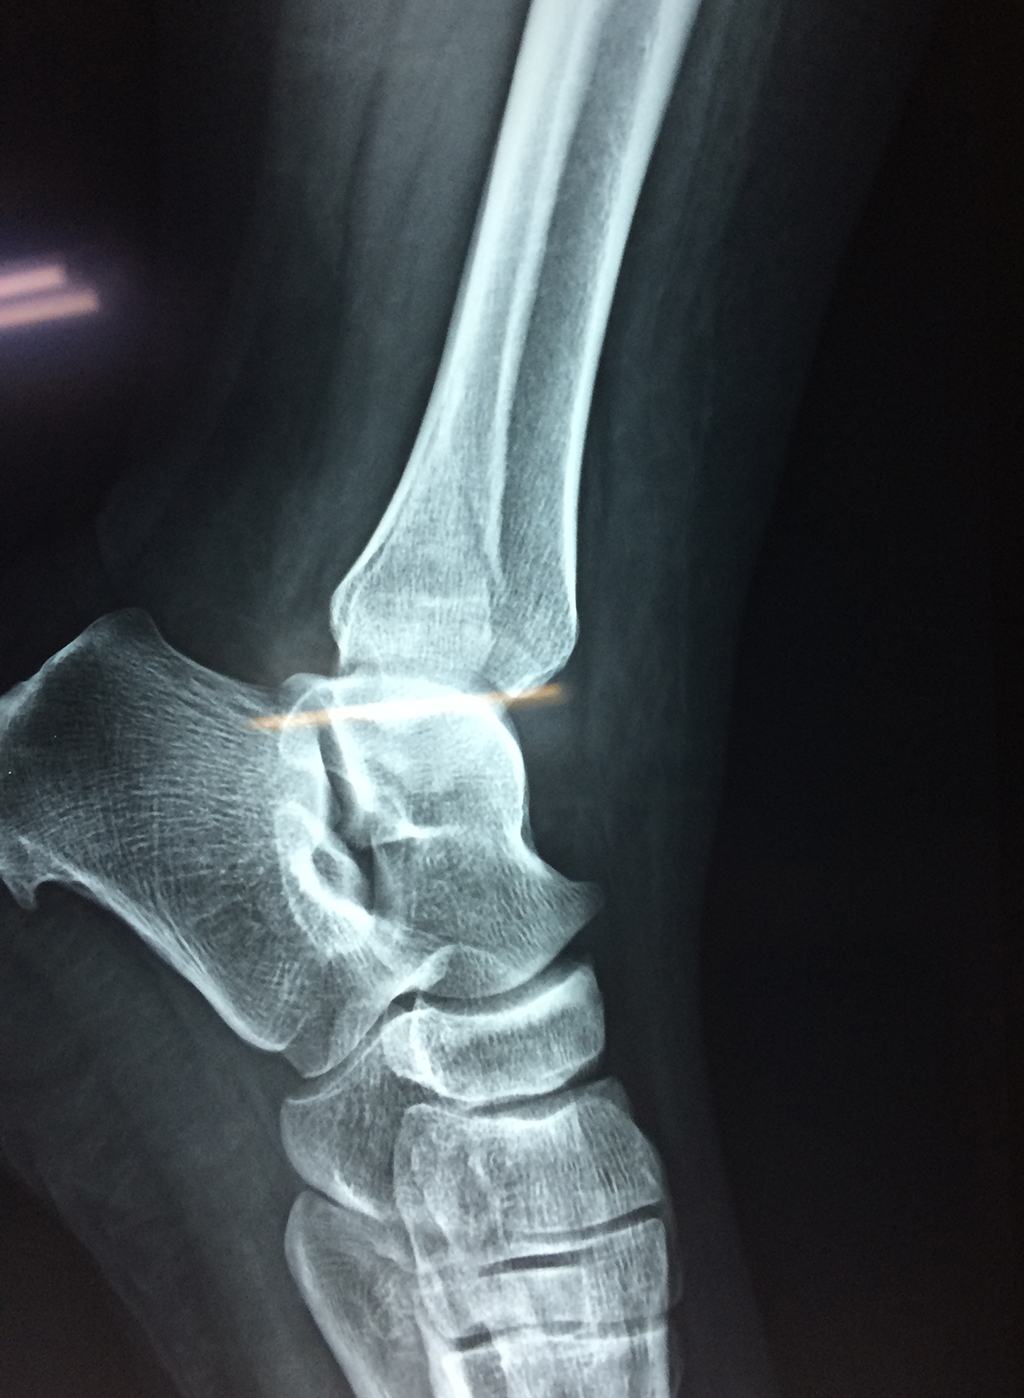

Una fractura de tobillo es la rotura de uno o más de los huesos del tobillo. Estas fracturas pueden ser:

- Los extremos de los huesos están desalineados entre sí (desplazados).

- La fractura se extiende hasta la articulación del tobillo (fractura intra-articular).

- Los tendones o ligamentos (tejidos que sujetan los músculos y los huesos entre sí) están rotos.

Cuando se necesita cirugía, es probable que esta implique el uso de clavijas de metal, tornillos o placas para sostener los huesos en su lugar mientras la fractura se consolida. Los elementos de soporte pueden ser temporales o permanentes.